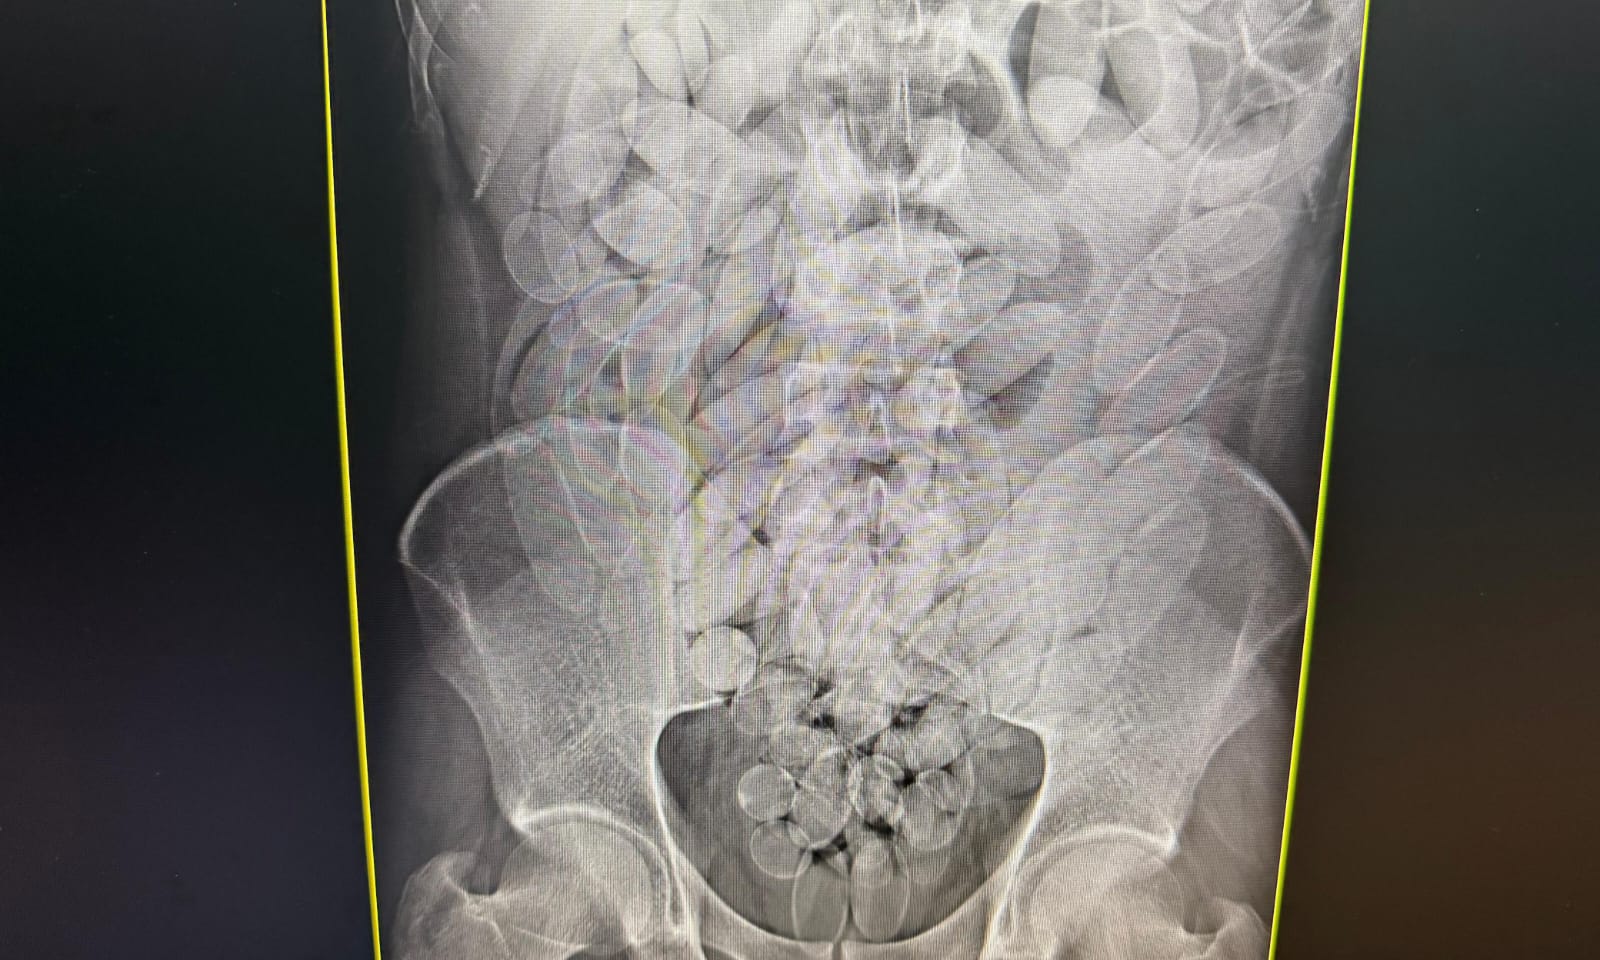

Divulgação/Receita Federal

Exame de raio-x confirmou presença de cápsulas de droga no estômago de suspeito